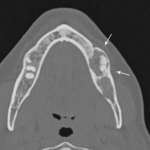

Sindrome di Eagle: una patologia di difficile interpretazione Premium

Una malattia rara caratterizzata da una sintomatologia molto varia che può facilmente simulare altre patologie del distretto cervico-facciale. Un ruolo molto importante ai fini della diagnosi può svolgerlo l’odontoiatra.